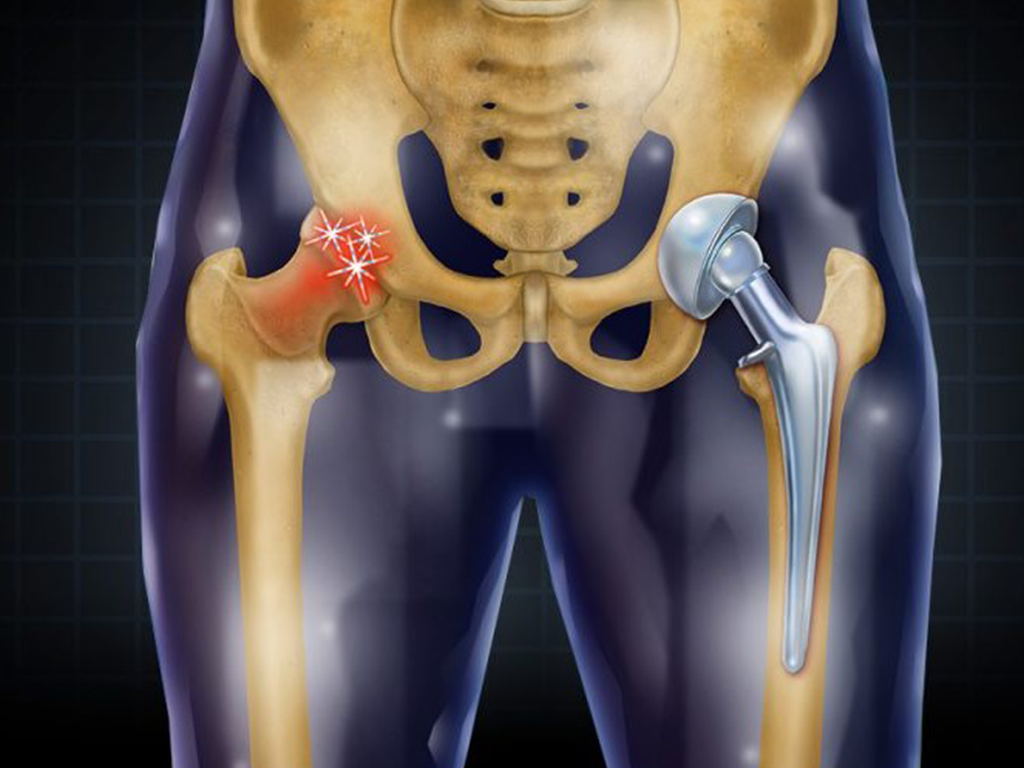

Замена таз сустава

Замена таз сустава 113 фотографий